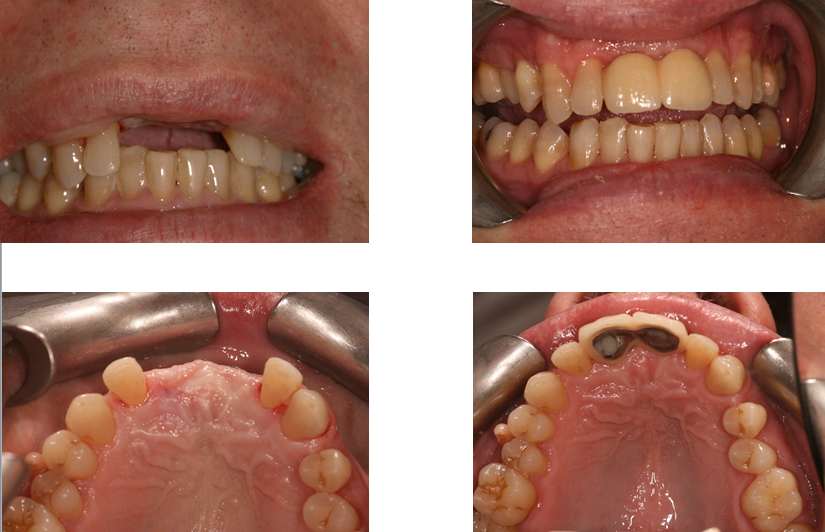

Guided Implant Surgery

Here at Aesthetic Dental Zone we embrace new concepts, guided implant surgery provides a solution where doctors can plan an implant virtually, and then accurately place an implant in the safest, predictable and efficient manner.

With guided surgery, we place the implant for the best aesthetic result and can predict accurately how much room will be needed for the crown and for any veneered superstructure that may go over the abutment.

From a single missing tooth to an edentulous jaw. It aids your Doctor to diagnose, plan the treatment and place your implants based on restorative needs and surgical requirements.

Following an initial Implant Consultation and CBCT scan (3D Scan of your jaw) we can get to work on your specific Implant case.Guided Implant Surgery takes away the need to be too invasive when placing your dental implants.

It is extremely accurate, more comfortable and the healing time is reduced.Guided Implant Surgery is a state of the art technology, trust in us to make your implant process as simple and easy as possible.